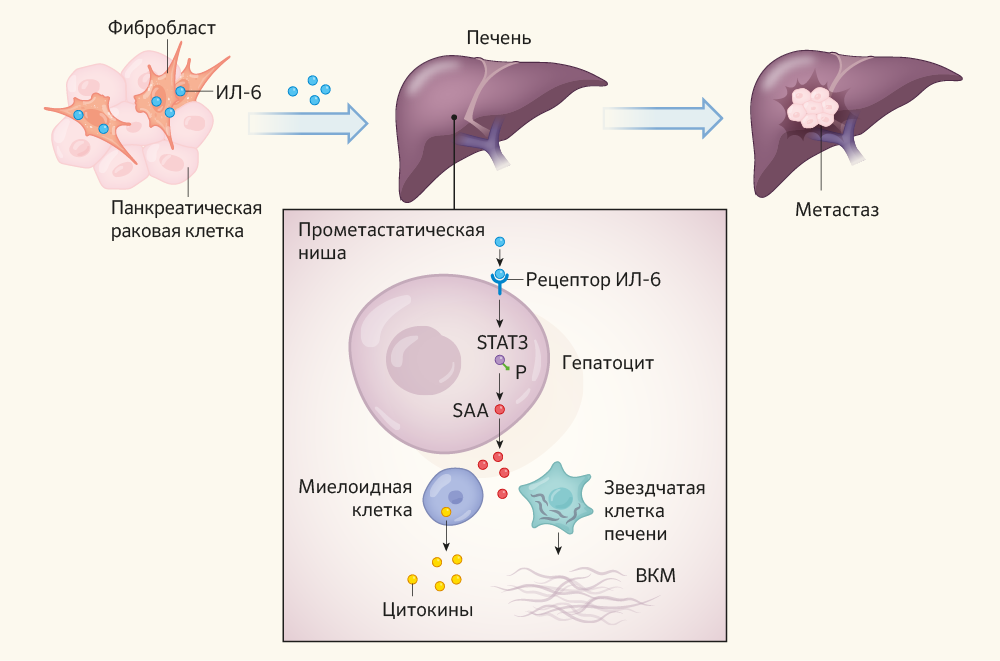

Метастатические поражения печени в ультразвуковом изображении характеризуются